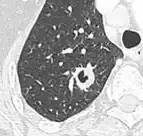

PET scan

If there is an intermediate risk of malignancy, further imaging with positron emission tomography (PET scan) is appropriate (if available). It can be done simultaneously as a CT scan in the form of PET-CT. Around 95% of patients with a malignant nodule will have an abnormal PET scan, while around 78% of patients with a benign nodule will look normal on PET (this is the test sensitivity and specificity).[15] Thus, an abnormal PET scan will reliably pick up cancer, but several other types of nodules (inflammatory or infectious, for example) will also show up on a PET scan. If the nodule has a diameter of less than one centimeter, PET scans are often avoided because of an increased risk of falsely normal results.[15][16][17] Cancerous lesions usually have a high metabolism on PET, as demonstrated by their high uptake of FDG (a radioactive sugar).

-

PET-CT of a tuberculoma.